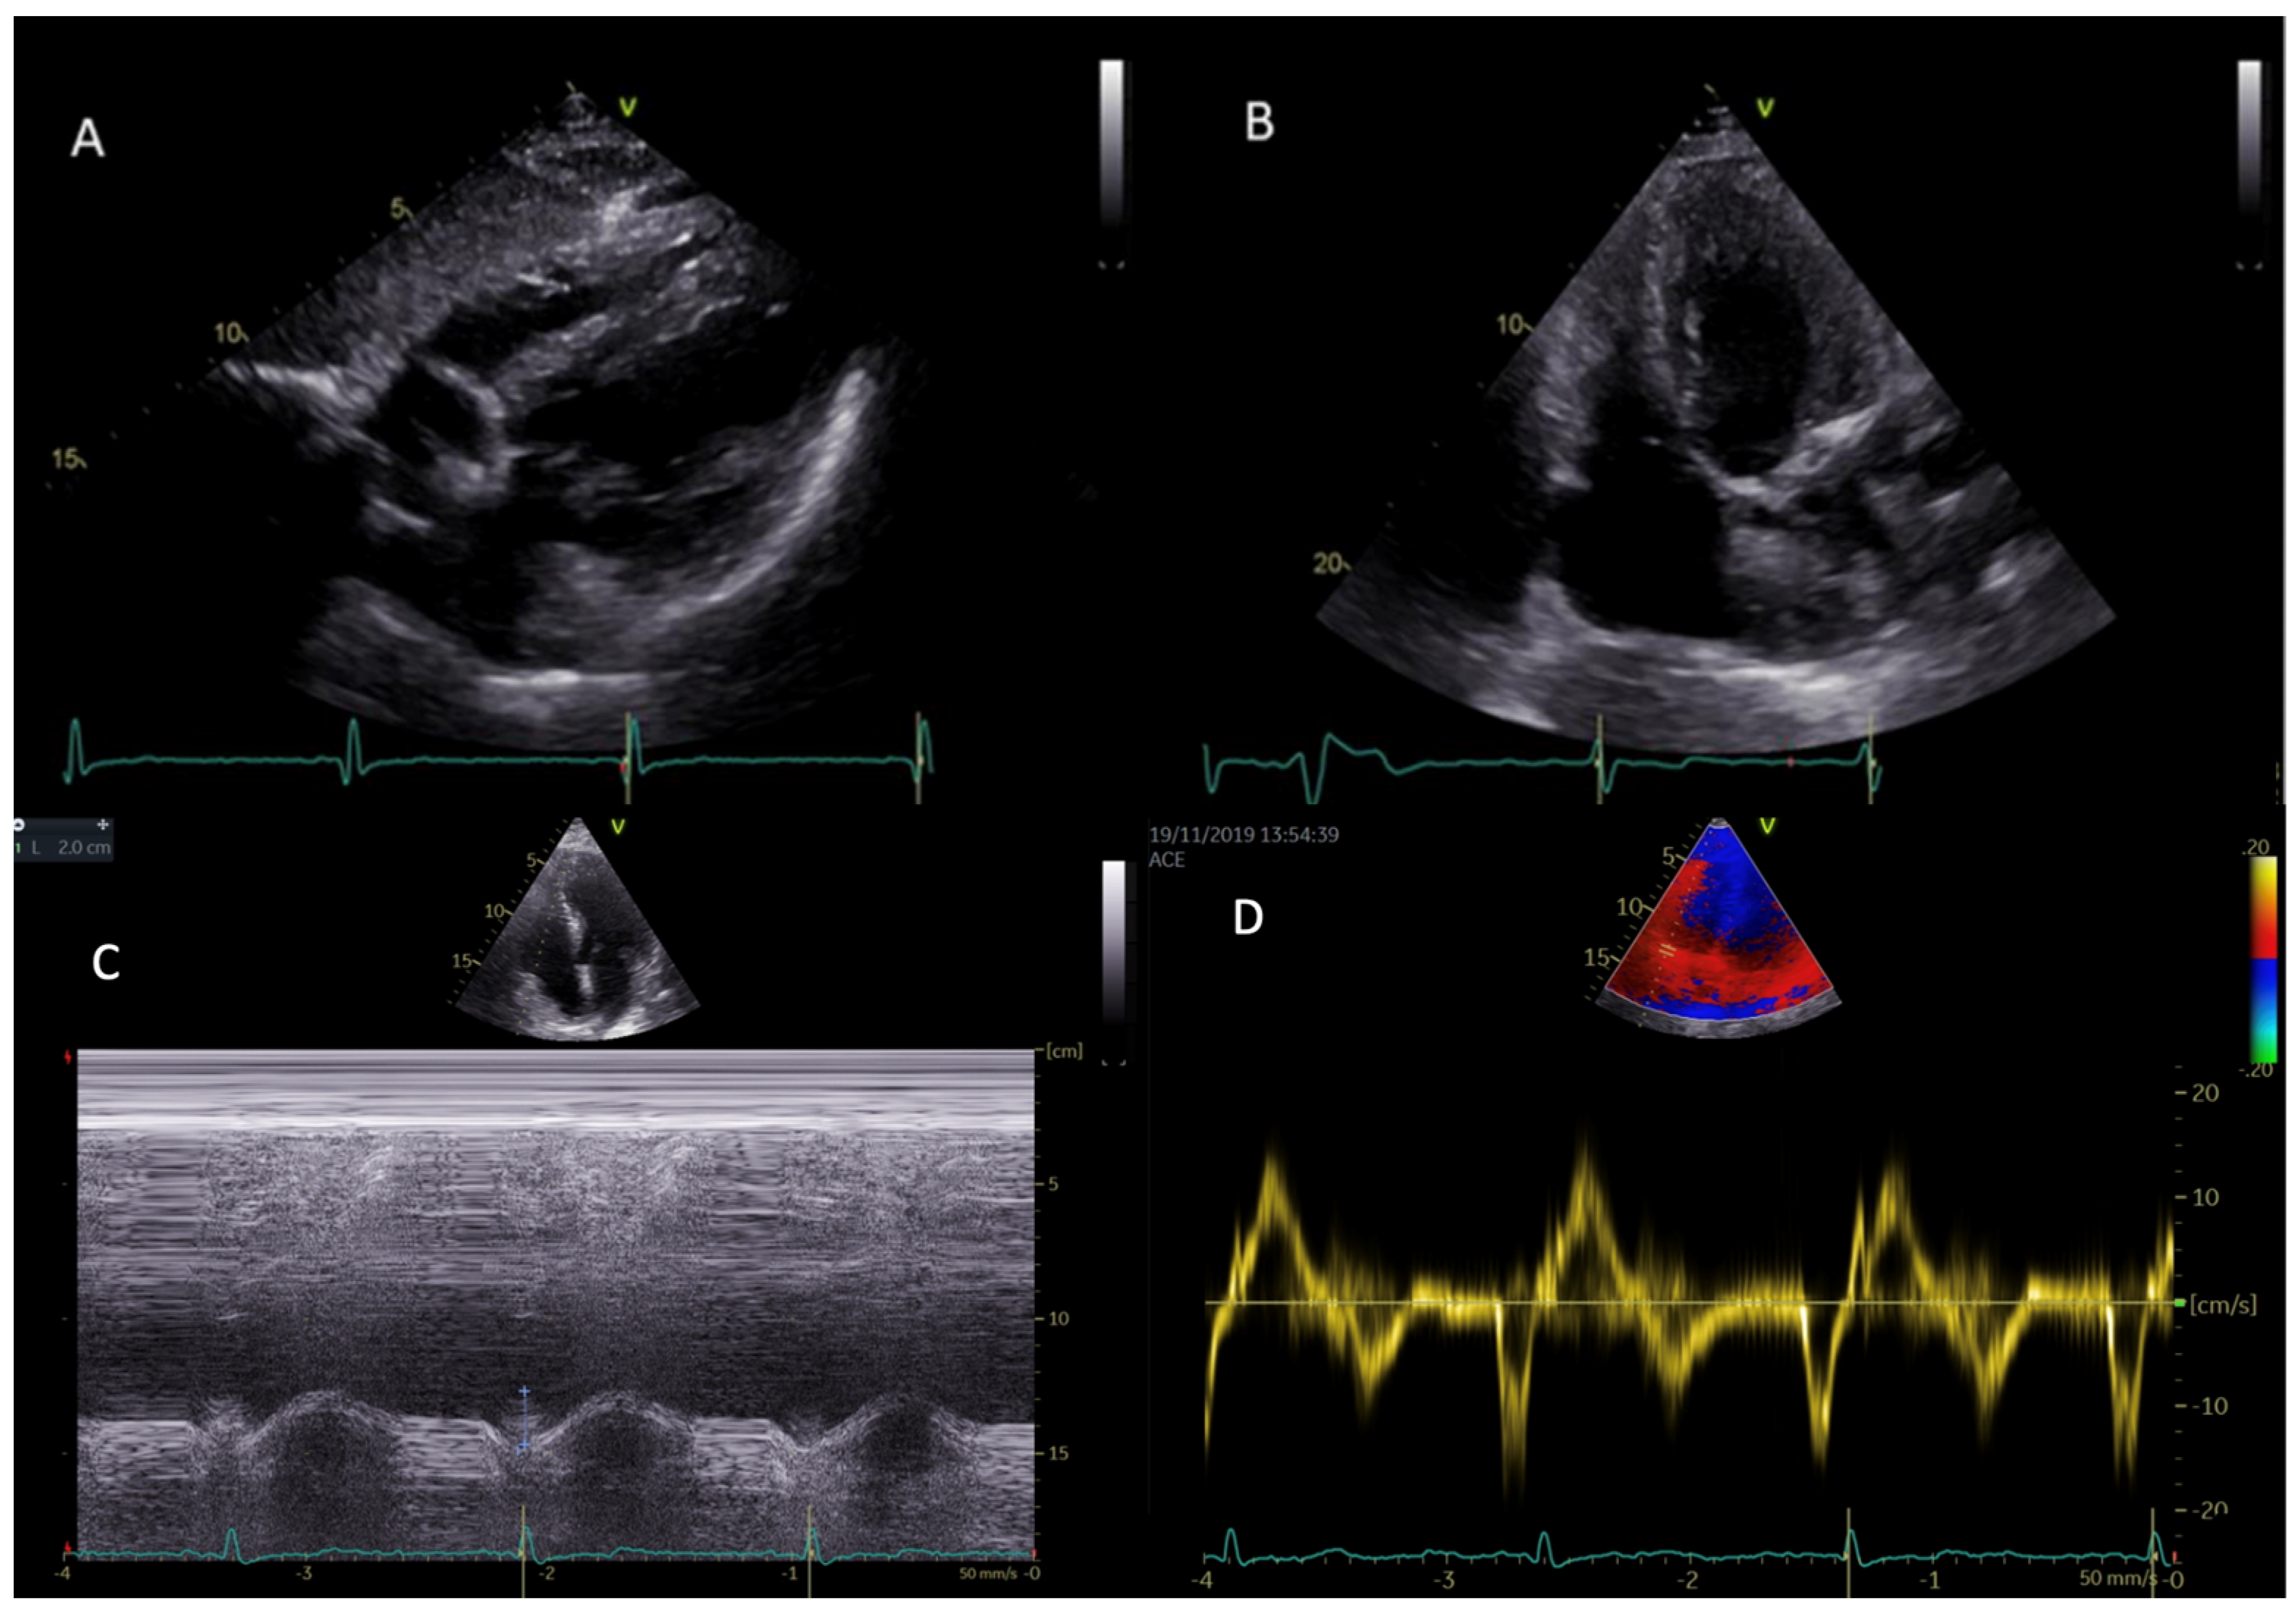

Right ventricular hypertrophy (RVH) (Figure 1) is common in patients with AFD and in most cases is related to disease severity and clinical worsening of symptoms. There is no sex difference when comparing the prevalence of RVH to LVH (which is more prevalent in males). Prevalence of RVH is estimated to account for 40–70% of all Fabry cardiac phenotypes. Another important epidemiological data is the strict correlation between RVH and age [38].

Figure 1.

Right and left ventricular hypertrophy in subcostal view (A) and in modified apical four-chambers view (B) in two different patients with AFD. Parametric indexes of right ventricular function, namely TAPSE (tricuspid annular plane systolic excursion) (C) and RVS’ (TDI: tissue Doppler imaging-derived tricuspid lateral annular systolic velocity wave) (D) in apical four-chambers view.